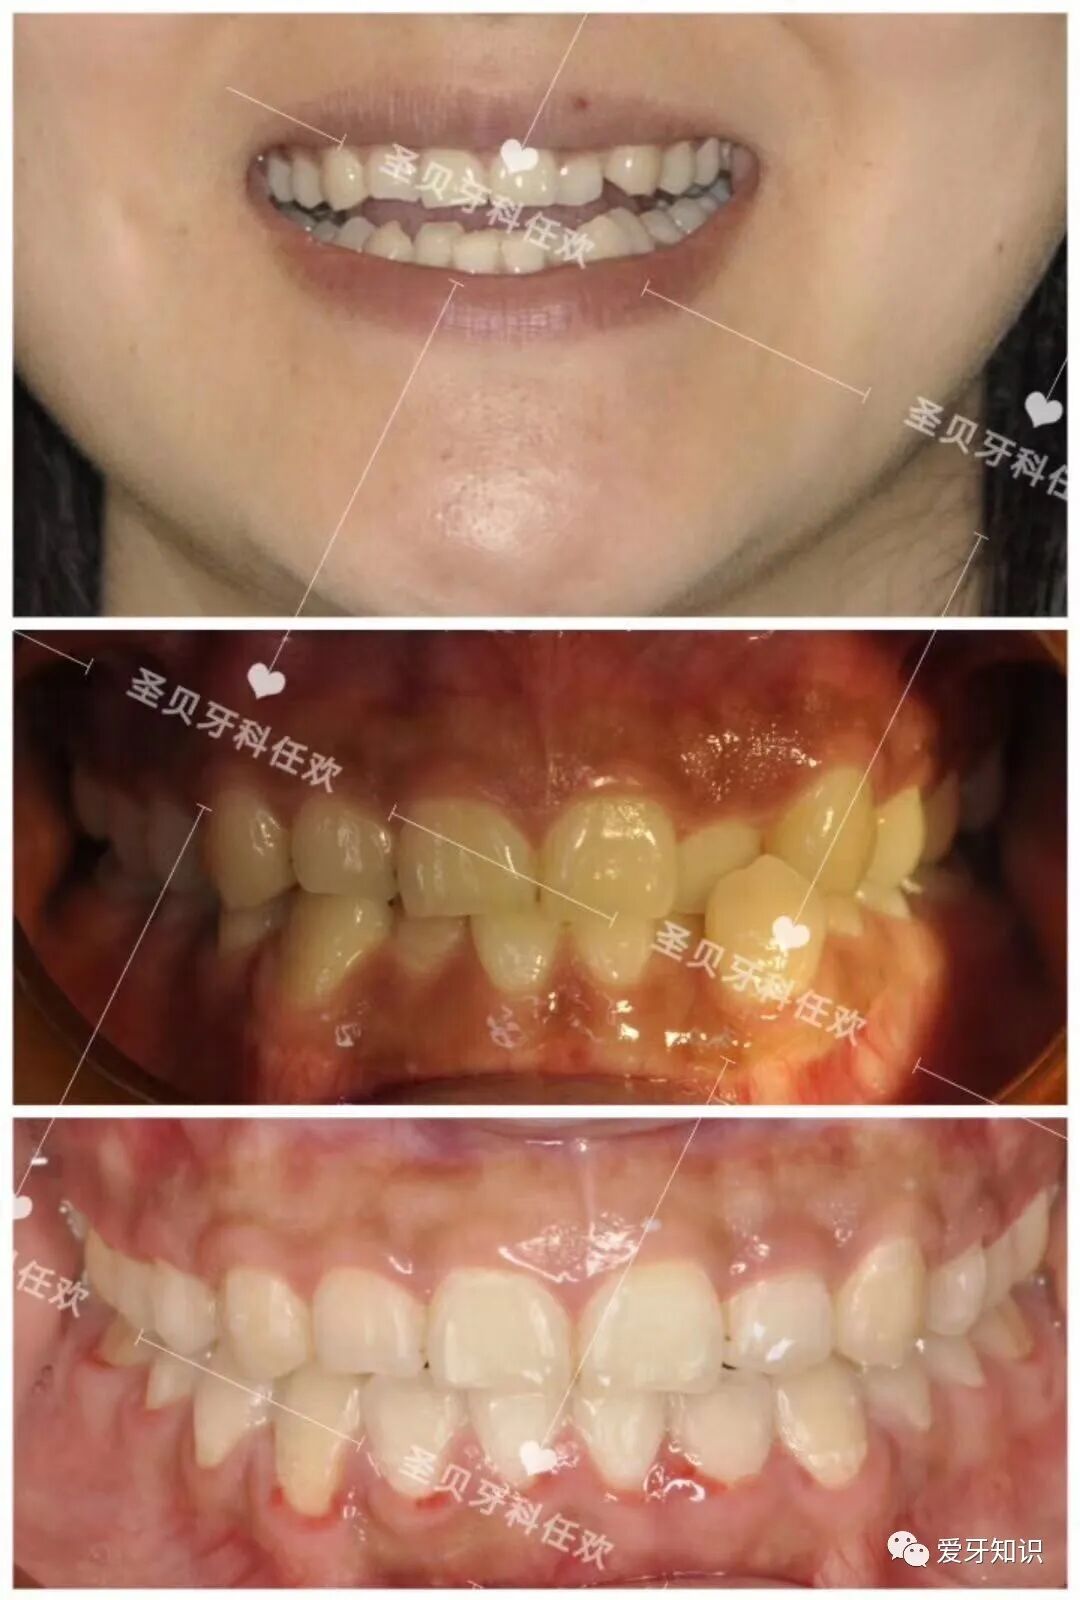

疫情过后,最近有很多小小美女,小帅哥都开始找我摘牙套了!都和牙套说分手了,下面就来给大家看几个摘牙套的小伙伴通过牙齿矫正有多大变化!

先上图给大家看看效果。

下面再来看看一个小姐姐矫正的变化,矫正改变真的是大,嘴型好看了,皮肤也好看了,你不羡慕吗?

矫正前,

矫正后

矫正前

矫正后!